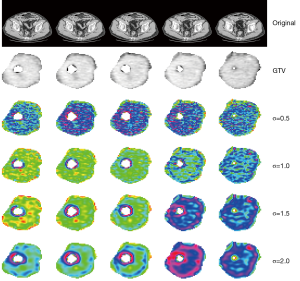

An example of the result of application of LoG filter on a rectal cancer CT scan is given in Figure 2. The upper line shows the initial CT scan over five different levels of the tumor. The second line shows the delineated gross tumor volume (GTV), the following lines show the appearance of processed images using LoG filter at different values of σ (0.5, 1.0, 1.5 and 2.0 pixels). It is evident, with growing the σ value, the appearance of the texture shows larger variations as the σ value grows up. It is interesting to understand as the use of filtering process can be an important prerequisite to achieve significant result in radiomics analysis. In this paper, indeed, only LoG processed images returned significant correlations with observed outcome while raw images didn’t: the features that showed significant prediction value for overall survival after Cox multivariate analysis were entropy, kurtosis, uniformity, skewness and standard deviation (SD) of pixel distribution histogram: among these features, entropy, kurtosis and skewness are mathematically invariant for pixels values when these are scaled linearly. This characteristic will show its value in the analysis of MR images, as it will be shown hereafter.